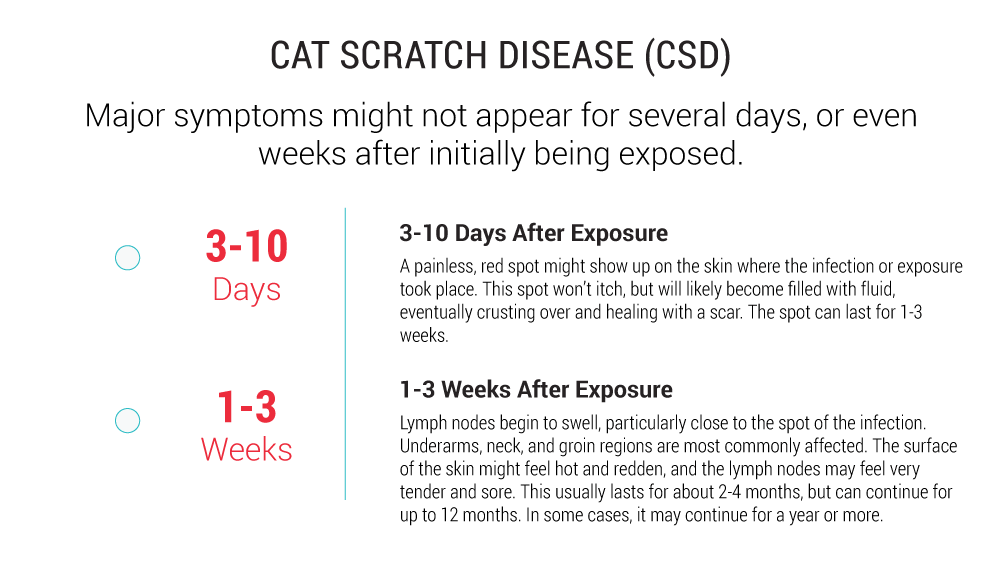

Cat Scratch Fever Cat Scratch Fever: Causes, Symptoms

Cat Scratch Fever: Causes, Symptoms  High-risk Zone for Cat Scratch Disease

High-risk Zone for Cat Scratch Disease  Cat Scratch Disease | Healthy Pets

Cat scratch disease: MedlinePlus  PDF] Cat scratch disease: The story

PDF] Cat scratch disease: The story  Cat Scratch Fever: Causes, Symptoms

Cat-Scratch Disease | Consultant360 Cat scratch fever: Causes, symptoms

Cat scratch fever: Causes, symptoms  Dealing with Cat Scratch Disease

Cat Scratch Disease (Cat Scratch Fever  Cat Scratch Disease | Healthy Pets

Cat Scratch Fever: Causes, Symptoms  Cat Scratch Disease in Primary Care

Cat Scratch Disease in Primary Care